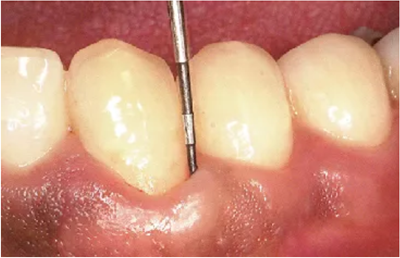

3、鄰接面牙周袋的檢測

鄰接面是最難以進(jìn)行檢測,測定結(jié)果也最容易出現(xiàn)誤差的部位。舌側(cè)遠(yuǎn)中等空間狹窄的部位,探針難以插入,而且有牙齒影子的影響,刻度難以讀取。

要充分注意到這些要點,并參考X片,盡量做到無漏查。

● 鄰接面正下方的探診

鄰接面的正面檢測方法。注意大約是在鄰接面部分的中央位置處,將探針略傾斜插入鄰接面的中央點。

檢測鄰接面正中點下方的牙周袋,探針是無法與牙軸平行插入的。但是緊靠著鄰接點平行于牙軸插入探針,可以檢測到難以檢測的鄰接面牙周袋深。

如果從斜側(cè)插入探針檢測沒有一定的標(biāo)準(zhǔn),那么每次測出的數(shù)值都會各不相同,得到的數(shù)據(jù)難以正確分析出問題所在。